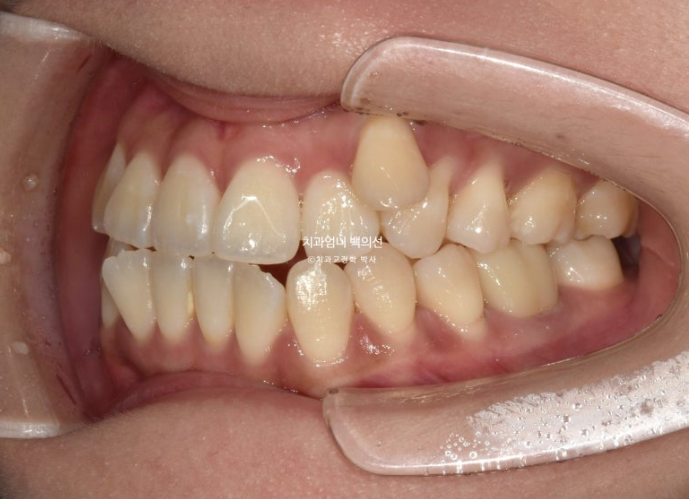

24년 11월 드디어 66개 장치를 모두 낀 후 모습입니다.

24.11

덧니는 제자리를 찾았고 아직 중심선 불일치가 보입니다.

덧니가 해결되었으니 큰 공사는 끝났네요.

어금니 교합이 뜨는 부분과 먼저 닿는 부분들을 개선하고자 재제작에 들어갑니다.